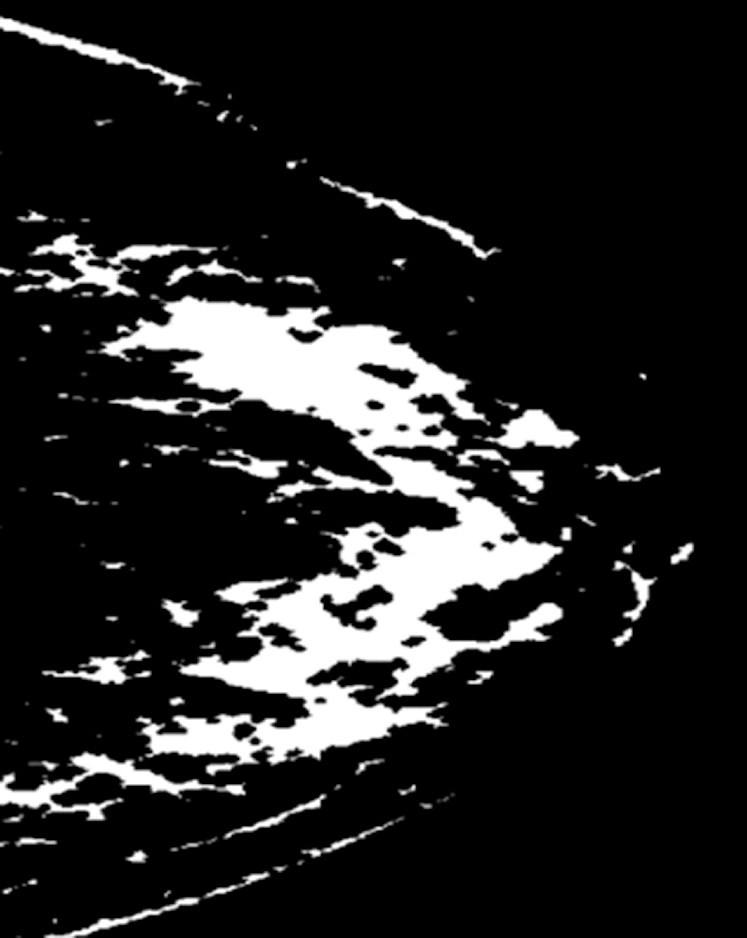

Fig. 7 depicts a mammogram image of a breast with normal tissues from the dataset DS, while Fig. 8 depicts a mammogram image from the DS dataset with cancer ROI that has been detected using T3. In Fig. 9, a mammogram is shown after applying texture features coupled with SIFT local features using T4.

Figure 8: A mammogram image from the DS dataset with cancer ROI using T3

Figure 9: A mammogram after applying texture features coupled with SIFT local features using T4